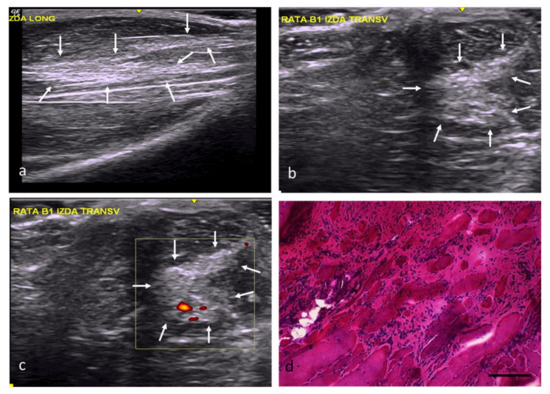

| Group | Identification of the Lesion | Edges of Lesion | Morphology of the Lesion | Increased Echogenicity | Echotexture Distortion | Vascularization |

|---|---|---|---|---|---|---|

| NC | — | — | — | Grade 0 | Grade 0 | Grade 0 |

| RC | Yes | poorly delimited | imprecise | Grade 1 | Grade 1 | Perilesional Grade 2 |

| FC | Yes | well delimited | angulated | Grade 3 | Grade 3 | Intralesional Grade 2 |

| AT | Yes | poorly delimited | imprecise | Grade 2 | Grade 1 | Intralesional Grade 1 |

| OS | Yes | well delimited | Variable (rounded, angled, or patchy) | Grade 3 | Grade 3 | Perilesional Grade 1 |

| DM | Yes | well delimited | Variable (rounded, angled, or patchy) | Grade 2 | Grade 3 | Intralesional Grade 1 |